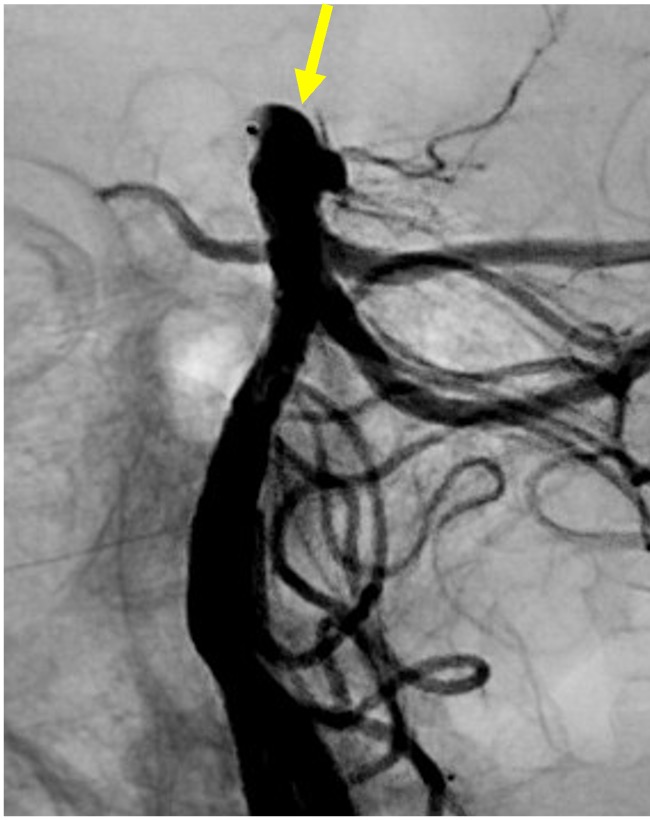

その1例を提示します。患者さんは65歳女性です。頭痛でMRIAを行い、血管撮影にて図1赤矢印の様に最大径7.8mm.ネック径4mmで、パイプラインというフローダイバーターステント(X線にて確認可能、図2〜5青矢印)を留置しました。その後、4ヶ月後の血管撮影ですが、図6緑矢印の様に動脈瘤は消失しています。

図2 |